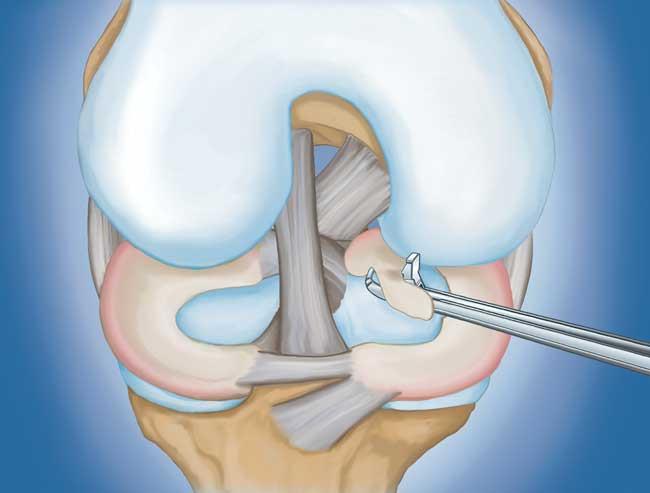

程序。 膝关节镜检查是最常进行的外科手术之一。在这个过程中,外科医生通过膝盖上的一个小切口(入口)插入一个微型相机。这提供了膝盖内部的清晰视图。然后外科医生通过两个或三个其他小入口插入手术器械以修剪或修复撕裂。

- 部分半月板切除术。 在这个过程中,受损的半月板组织被修剪掉。该程序通常允许在手术后立即负重和全方位运动。

- 半月板修复。 一些半月板撕裂可以通过将撕裂的碎片缝合(缝合)在一起来修复。撕裂能否成功修复取决于撕裂的类型,以及受伤半月板的整体状况。因为半月板必须一起愈合,修复的恢复时间比半月板切除术长。